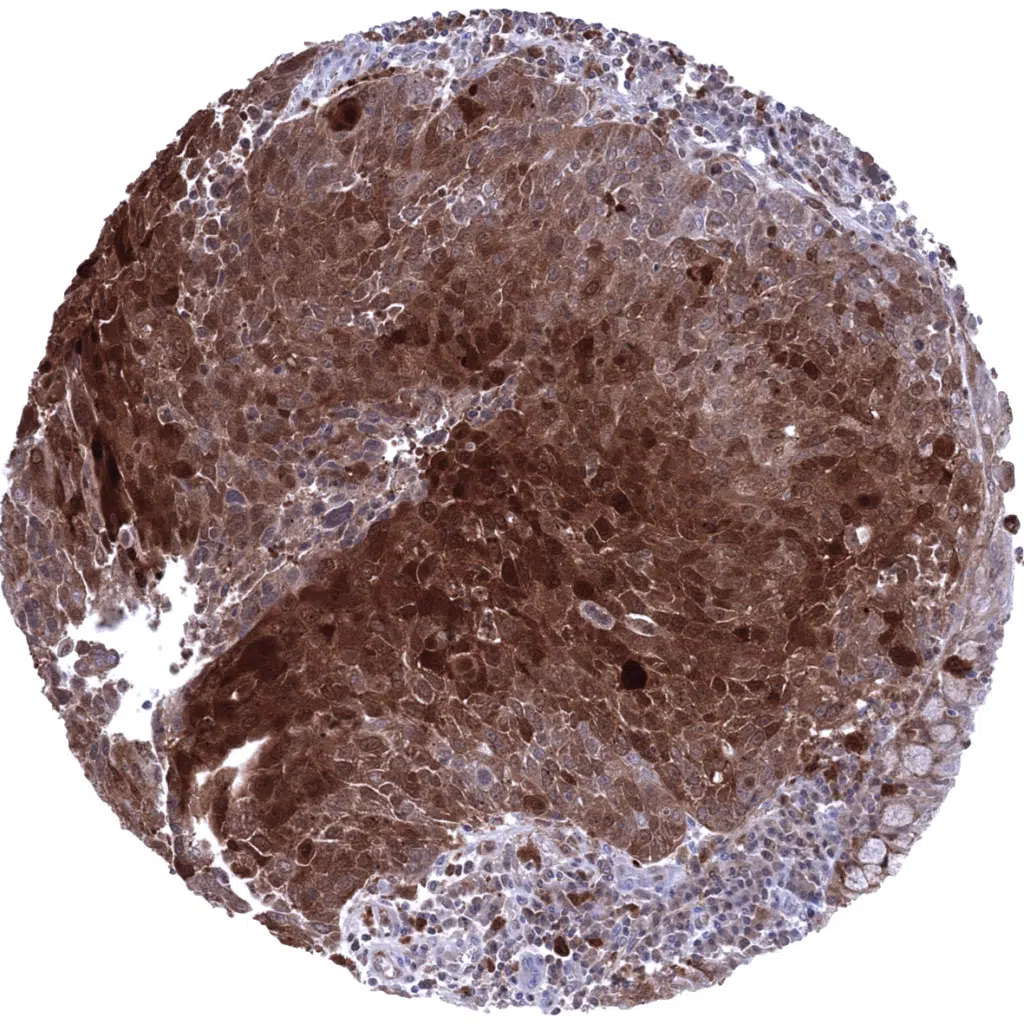

Lung- Squamous cell carcinoma with strong Cystatin A immunostaining of tumor cells. Cystatin A is also abundant in various cell types of the tumor stroma.